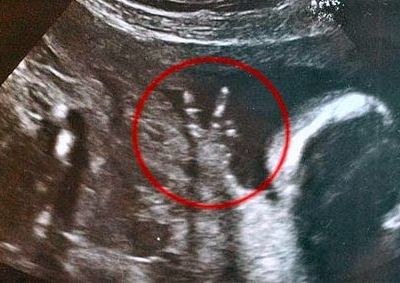

ΑΝΑΠΤΥΞΗ Απίστευτο: Έμβρυο από την κοιλιά της μάνας του κάνει το σήμα της νίκης με τα δαχτυλάκια του!